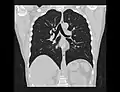

Chest CT (axial lung window)

Chest CT (coronal lung window)- Chest CT (axial lung window)